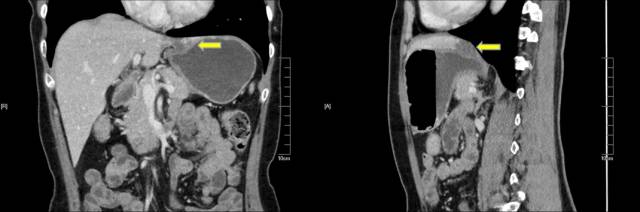

3.肝血管瘤和肝囊肿联合外压

这种情况相对少见,下面病例我们可见看到高位胃体前壁哑铃状隆起(图 A),EUS探查见囊性病灶(白箭头)和实性病灶(黄箭头)共同外压(图 B),CT证实来源于肝左叶的囊肿和血管瘤联合外压(图 C-D)。

A:高位胃体前壁哑铃状胃壁隆起;B:超声探查见来源于肝脏的囊性和实性病灶;C-D:CT证实来源于肝脏的囊肿和血管瘤的联合外压